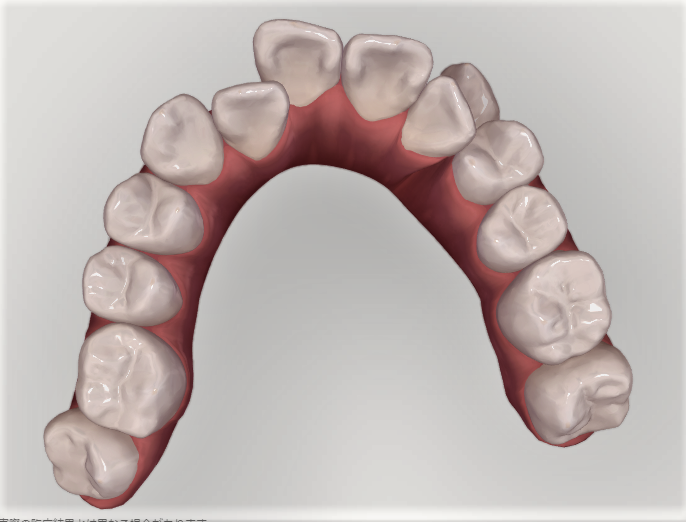

上の歯。前歯に内側に引っ込んだ歯がある。

上の歯。引っ込んだ歯が歯並びの中に納まっている。

上の歯の比較